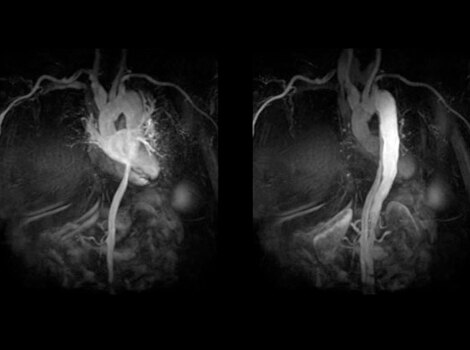

If considering catheter ablation as a treatment option, pre-procedure planning can involve use of MR or CT imaging to identify anatomical targets for the procedure and understand the extent of AF. These images can help guide decisions on necessity of left atrial appendage closure in certain populations.3

Revolution CT & CardioGraphe4

Achieve one-beat, whole heart acquisition for imaging or comprehensive cardiac assessment with or without beta blockers at any heart rate.5

Read More

Revolution CT & CardioGraphe7

Achieve one-beat, whole heart acquisition for imaging or comprehensive cardiac assessment with or without beta blockers at any heart rate.8

Revolution CT & CardioGraphe3

Achieve one-beat, whole heart acquisition for imaging or comprehensive cardiac assessment with or without beta blockers at any heart rate.4 Read More

Achieve one-beat, whole heart acquisition for imaging or comprehensive cardiac assessment with or without beta blockers at any heart rate.4